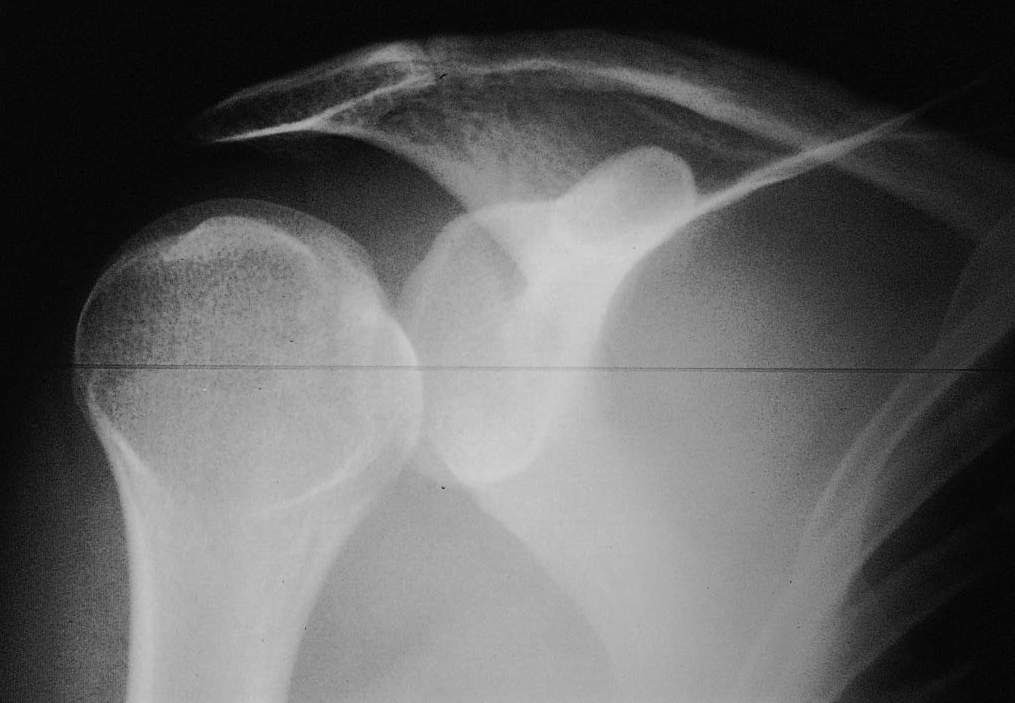

X Ray Shoulder Posterior Dislocation . — posterior shoulder dislocations account for about 2% to 5% of all shoulder dislocations. The glenohumeral joint will be. — a posterior shoulder dislocation was diagnosed when an orthogonal view (axillary) of the shoulder was taken (fig 3 ⇓). — anterior dislocation will result in the humeral head being displaced deep into the far field (away from one's probe), whereas posterior. An axial view may provide additional information where there is diagnostic uncertainty. Trauma (posterior dislocation) 50% of cases that present for evaluation. In 30% of patients, recurrent posterior dislocations.